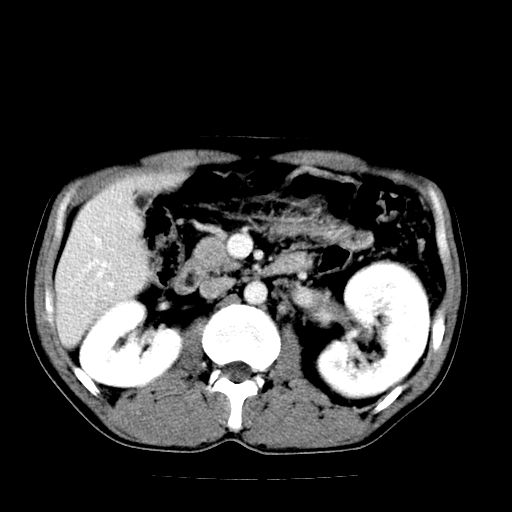

以下是引用天南地北在2007-4-30 13:36:00的发言:[br]支持慢性胰腺炎伴有假性囊肿

以下是引用andymaomao在2007-4-30 14:28:00的发言:[br]支持:1.慢性胰腺炎并假性囊肿形成可能;[br] 2.左肾形态稍增大,旋转不良。